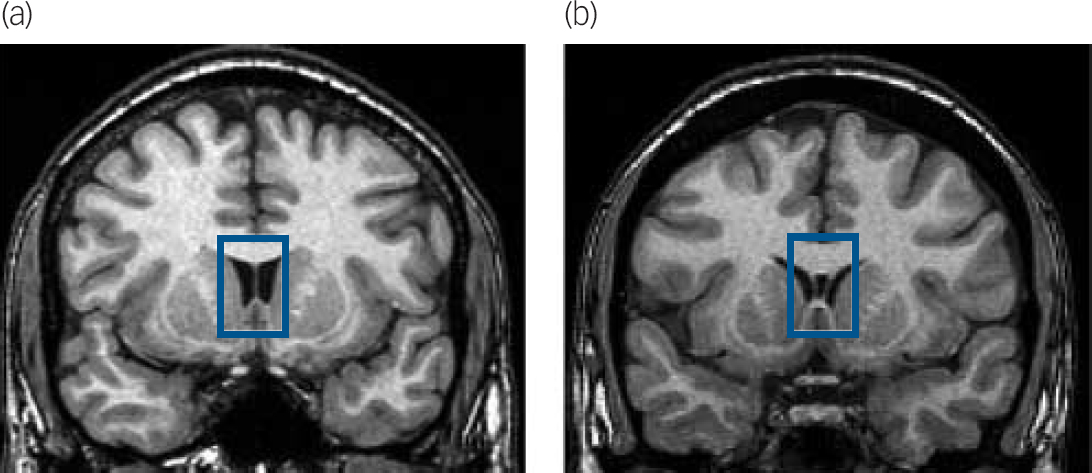

Fig. 1 Illustration of normal septum pellucidum (thin membrane separating the lateral ventricles) in a non-antisocial control (a) and the cavum septum pellucidum in an individual with antisocial personality disorder (b).

Coronal magnetic resonance image slices are at the level of the head of the anterior limb of the internal capsule, caudate, putamen, accumbens, and insula. Highlighted within the bue box is the septum pellucidum, dividing the lateral ventricles and bordered superiorly by the body of the corpus callosum and inferiorly by the fornix. The normal control (a) shows a fused septum pellucidum, whereas the participant with antisocial personality disorder (b) shows a fluid-filled cavum inside the two leaflets of the septum pellucidum.